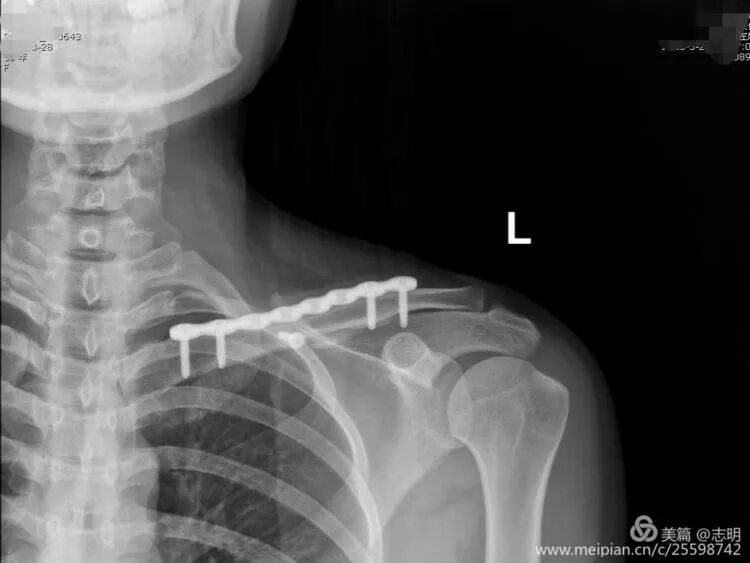

(Example of pre-operative imaging, likely an X-ray showing fracture).

- Standard Radiographs: Acquire high-quality anteroposterior (AP) views of the shoulder with a 10-15 degree cephalic tilt, along with a true AP clavicle view (0 degrees tilt). These projections are crucial for initial assessment of the fracture pattern, the degree and direction of displacement, and any significant shortening.